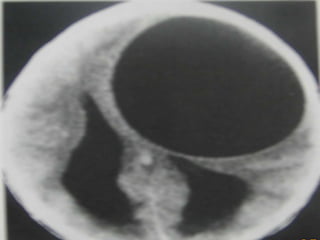

Echinococcosis

– Larval stage- hydatid cyst

– Cerebral hydatid- seen in only 2% cases

– Imaging

• Single thin walled spherical CSF density cyst

• Large cystic lesion lying subcortically in middle cerebral

territory of parietal area (can reach large size often

over 6 cm in diameter).

• No edema or enhancement or adjacent calcification.

• Enhancement and perilesional edema are seen only if

the cyst is superinfected.

Echinococcosis – Larval stage-hydatid cyst – Cerebral hydatid- seen in only 2% cases – Imaging • Single thin walled spherical CSF density cyst • Large cystic lesion lying subcortically in middle cerebral territory of parietal area (can reach large size often over 6 cm in diameter). • No edema or enhancement or adjacent calcification. • Enhancement and perilesional edema are seen only if the cyst is superinfected.